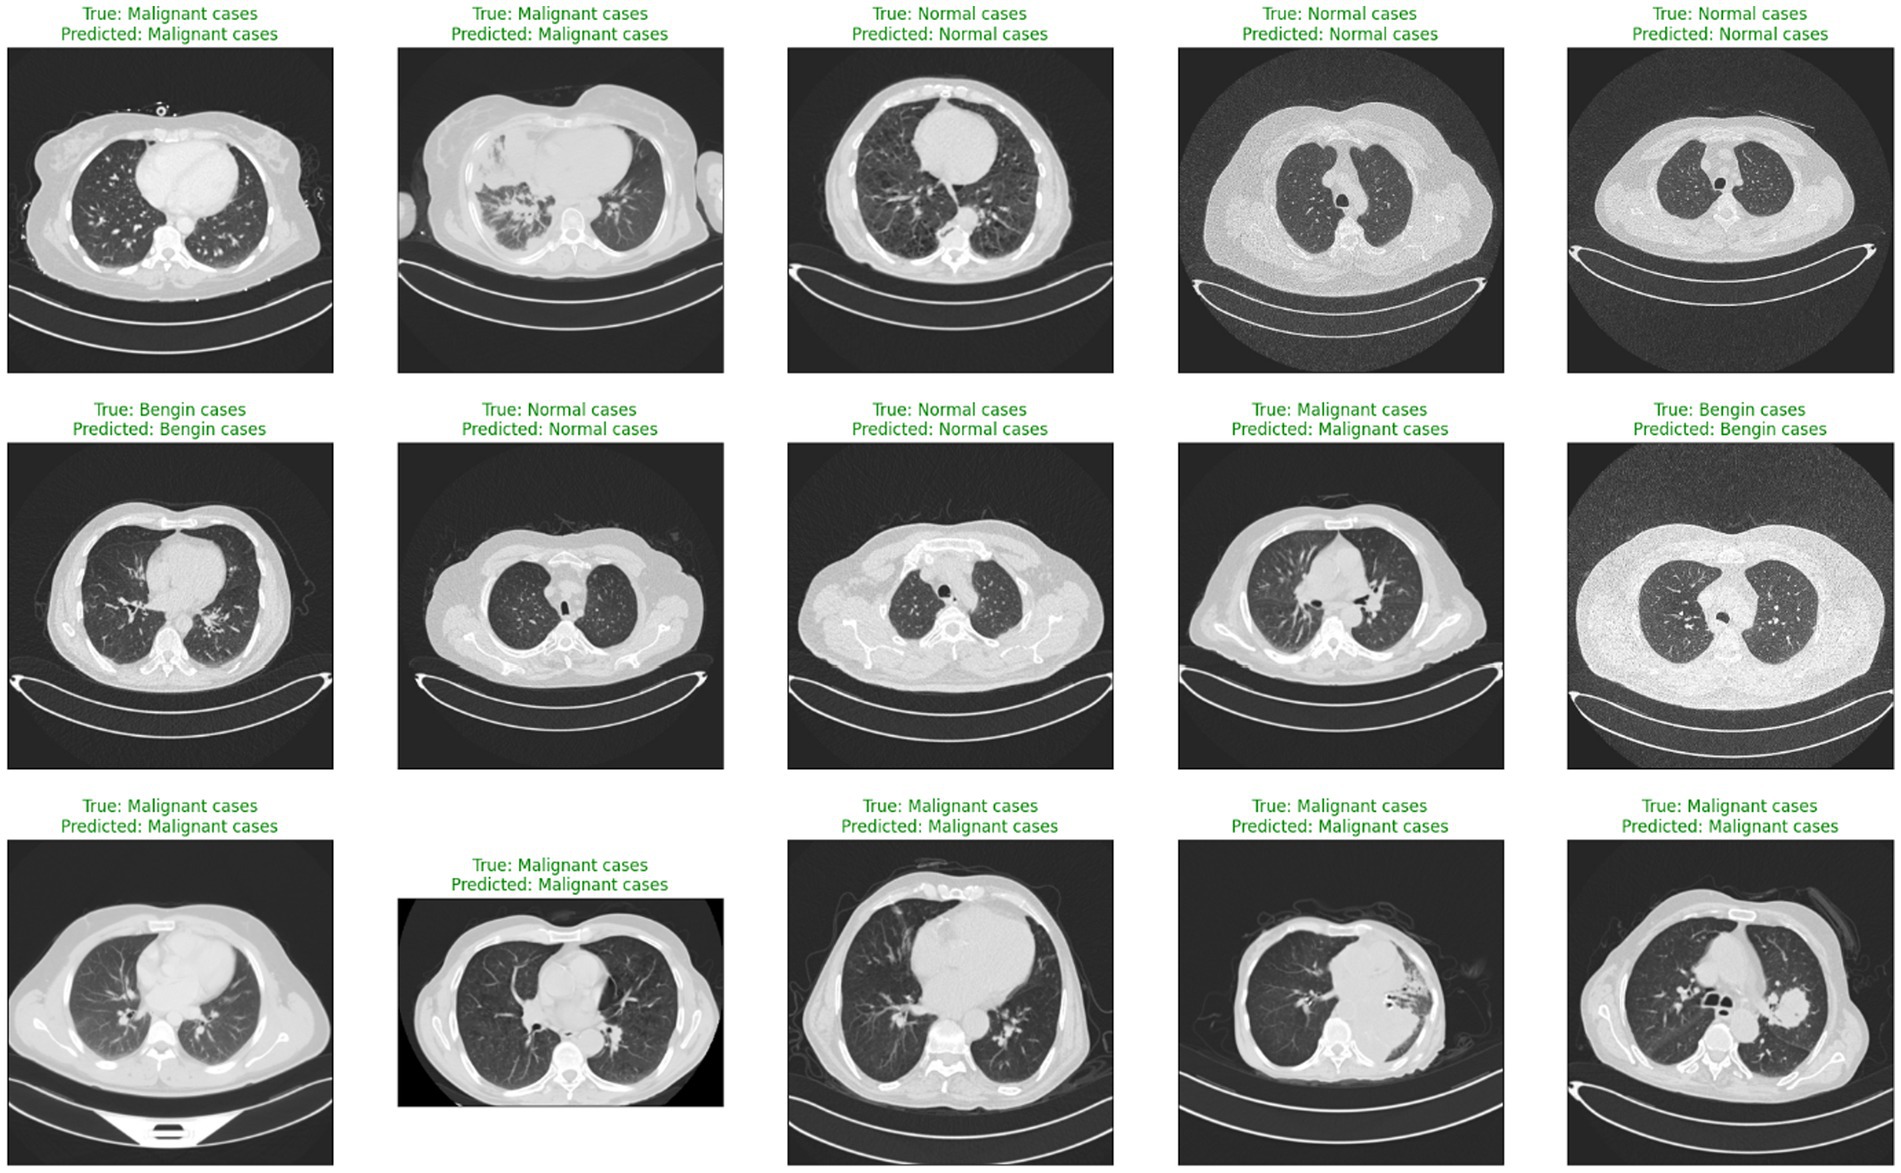

When comparing the recommended AI-driven diagnostic model for lung cancer with traditional diagnostic methodologies, certain gains show, with major downsides that demand thorough examination. Conventional diagnostic methods, such radiologists manually interpreting CT images, heavily depend on the skills and knowledge of medical experts. Although these methods have long served as the foundation of medical diagnostics, their diagnostic accuracy can vary, and they frequently involve laborious procedures. With accurate predictions for most cases in several categories, Figure 8 illustrates the model’s effectiveness in detecting lung cancer stages.

Figure 8

Sample CT images showing true labels versus model predictions.